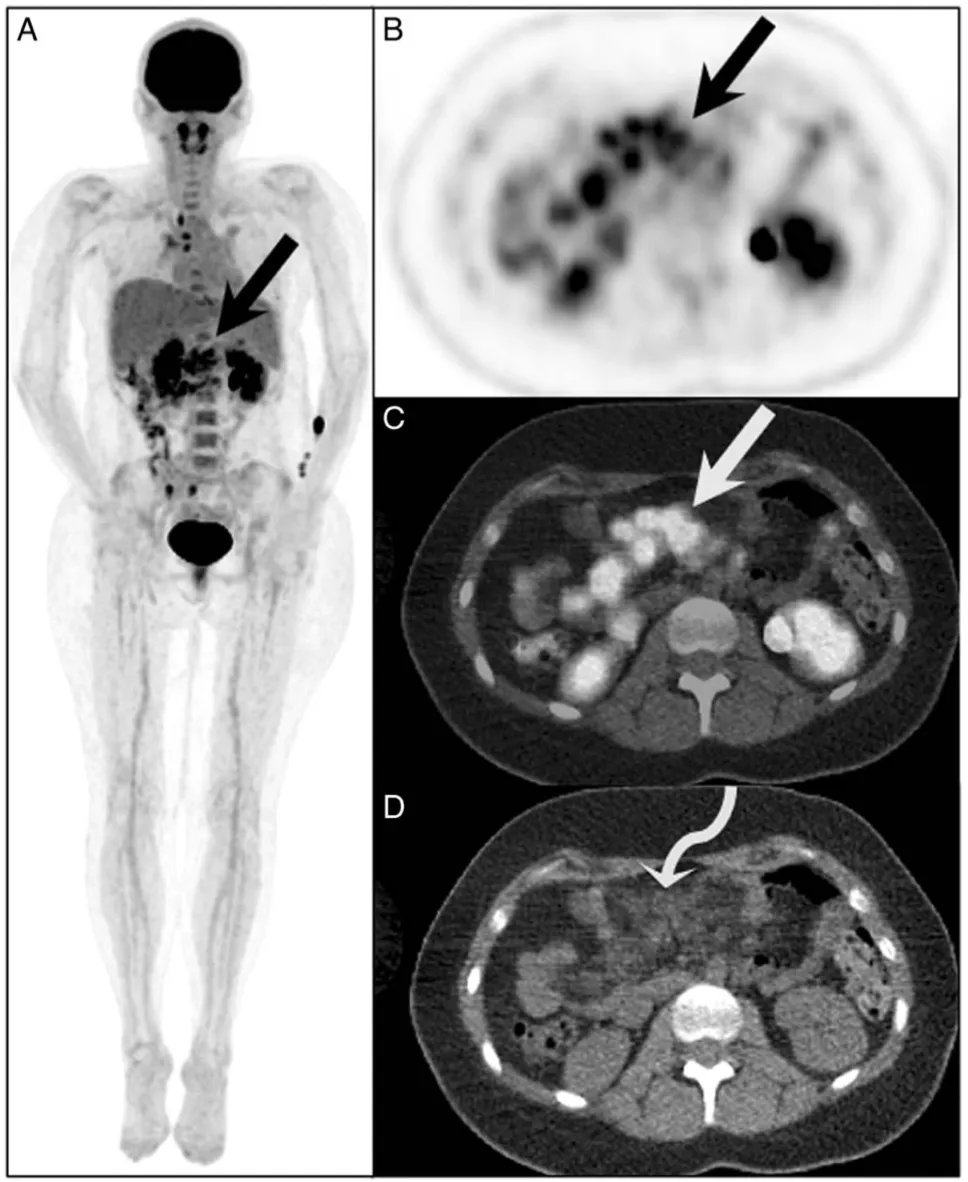

为了进一步确诊(或者说为了确认“死刑”),医生安排了 FDG PET/CT。

上腹部那一团浓聚的黑影,触目惊心(图2A)。肠系膜上的结节摄取极其活跃,SUVmax 高达7.4(图2B)!

图2.患者PET/CT图像显示肠系膜区多发高代谢灶

CT显示强化,PET显示高代谢(SUV 7.4),在传统的影像诊断逻辑里,这几乎就是“肿瘤多发转移”的铁证。